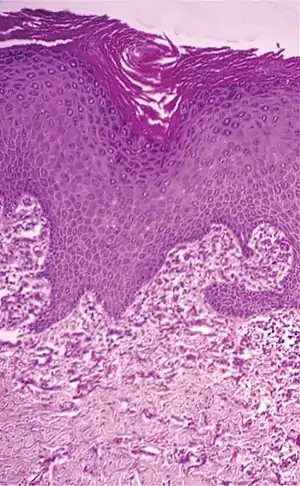

| Histopathology of perforating calcific elastosis: Clumping of short elastic fibers in the dermis.[2] | |

a,b)Perforating calcific elastosis- short elastic fibers in the dermis